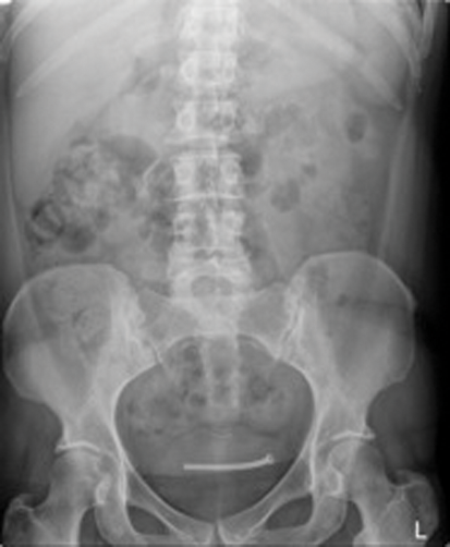

Case 2

Image 2.

- What do these X-Ray KUB films show?

Image 2: Bilateral ureteric stents, right ureteric stent deviation secondary to retroperitoneal lymphadenopathy and part of an inferior vena cava (IVC) filter in-situ. This patient has metastatic testicular cancer with bulky retroperitoneal lymphadenopathy and deep vein thrombosis (DVT).